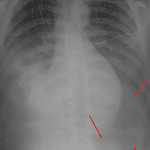

- Large left-sided pneumothorax manifesting as a deep sulcus sign on this supine radiograph

- Pneumothorax (deep sulcus sign)

Large left pneumothorax. No mediastinal shift.

Hazy bibasilar opacities likely represent a combination of layering pleural fluid and atelectasis. Superimposed aspiration is not excluded in this trauma patient.